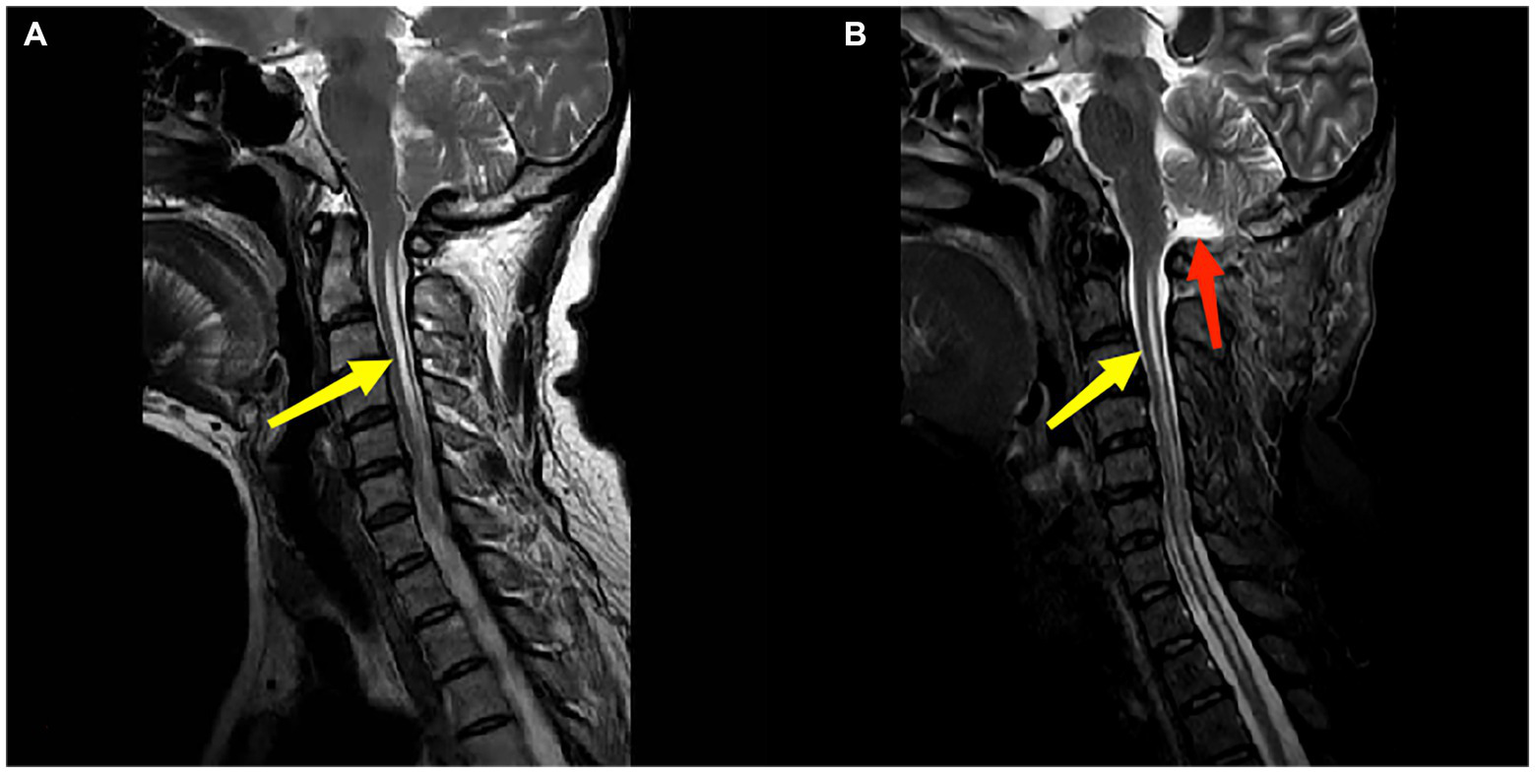

Figure 2

Panels (A,B) are the preoperation and postoperation MRI images of a 51-year-old female patient who underwent PFDD treatment. The red arrow in (B) indicates the postoperative recreated cistern magna. The yellow arrow indicates the patient’s syringomyelia, and there was a reduction in the diameter of syrinx postoperatively.